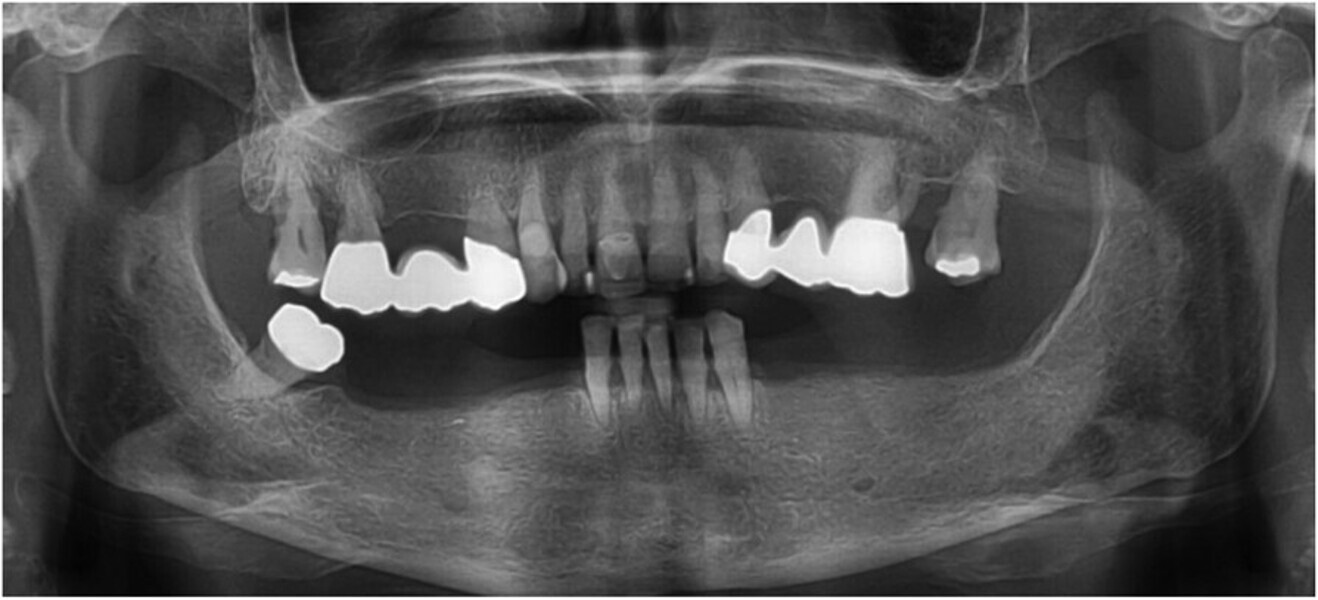

Fig. 10: Post-op panoramic radiograph.